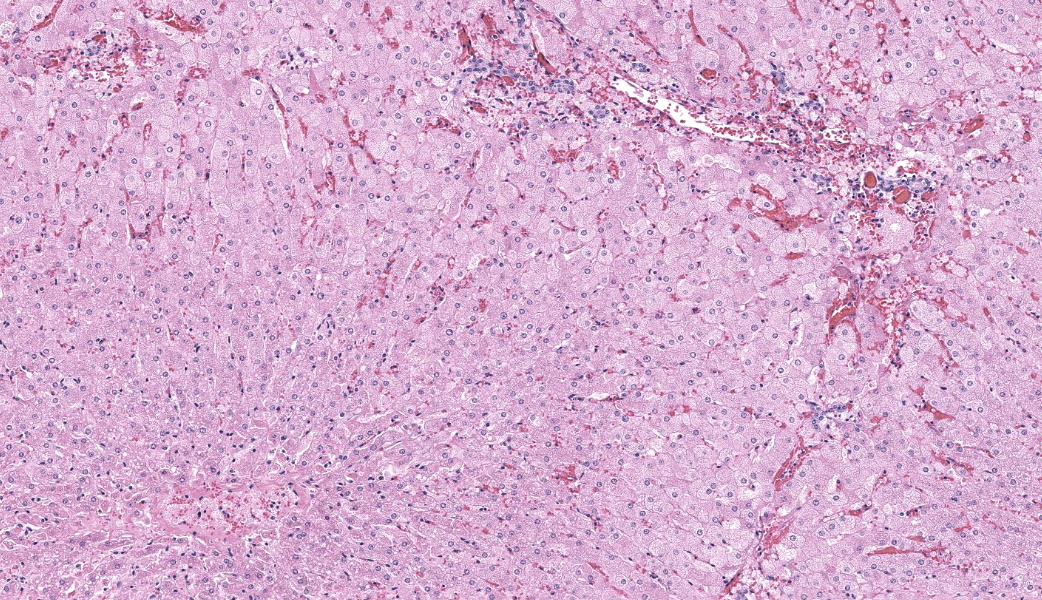

Liver: Diffusely, hepatocytes are moderately swollen and contain numerous small (~1µm) discrete to coalescing cytoplasmic vacuoles (microvesicular hepatopathy). Nuclei remain centrally located. Within the centrilobular interstitium, hepatocytes are occasionally individualized, rounded, shrunken, and/or hypereosinophilic with karyolysis (necrosis). There is mild, patchy periportal hemorrhage.

Osmium tetroxide post-fixation revealed prominent staining of microvesicular lesions, confirming the vacuoles as lipid droplets.

Oil Red O revealed prominent staining of microvesicular lesions, again confirming the vacuoles as lipid droplets.

Liver: Microvesicular hepatopathy, moderate, acute, diffuse, with mild centrilobular hepatocellular necrosis.

Liver: Hepatocellular lipidosis, microvesicular, acute, diffuse, severe.